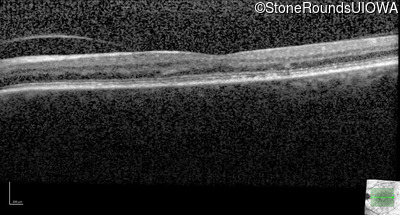

Age at visit: 59 years (Visit 3)